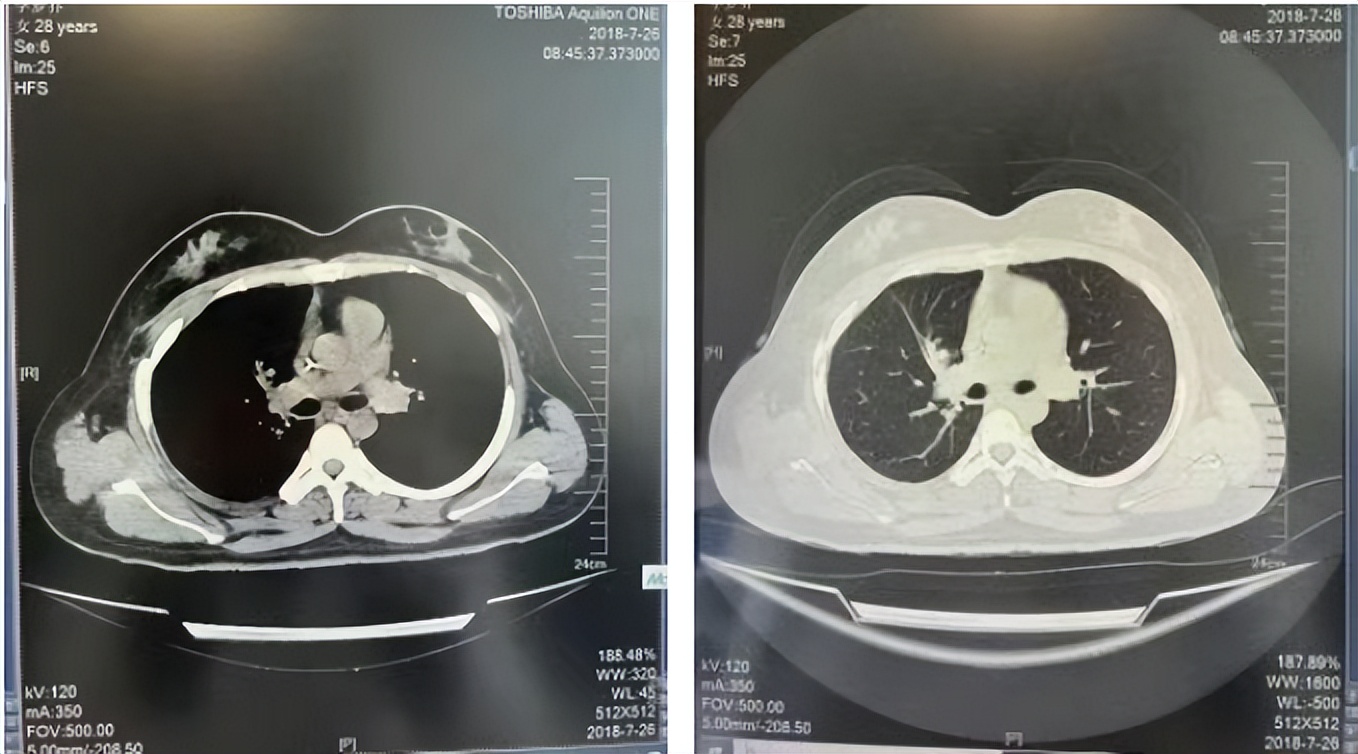

2016年1月复查CT提示支气管截断可见新发小结节,一线治疗采用培美曲塞+DDP方案化疗4周期(培美曲塞3.36,DDP 480mg)。化疗后复查胸部CT:右肺见不规则结节样影,最大层面大小约19mm*8mm,较前比较明显增大,疗效评估PD。2017.3-2017.4予单药多西他赛化疗3周期,疗效评估SD。2018年5月末复查CT提示结节较前增大,评效为PD,2018年6-10月予多西他赛+CBP化疗4周期,疗效评估SD。2022年5月患者出现活动后气短,复查胸部CT示右肺膨胀不良;右侧胸腔积液增多。胸腔积液包埋病理示符合肺腺癌细胞。行NGS基因检测:EML4:exon13-ALK:exon20融合。PD-L1(克隆号22C3)TPS<1%。

2018.07

2022.05

2022.08

2023.05